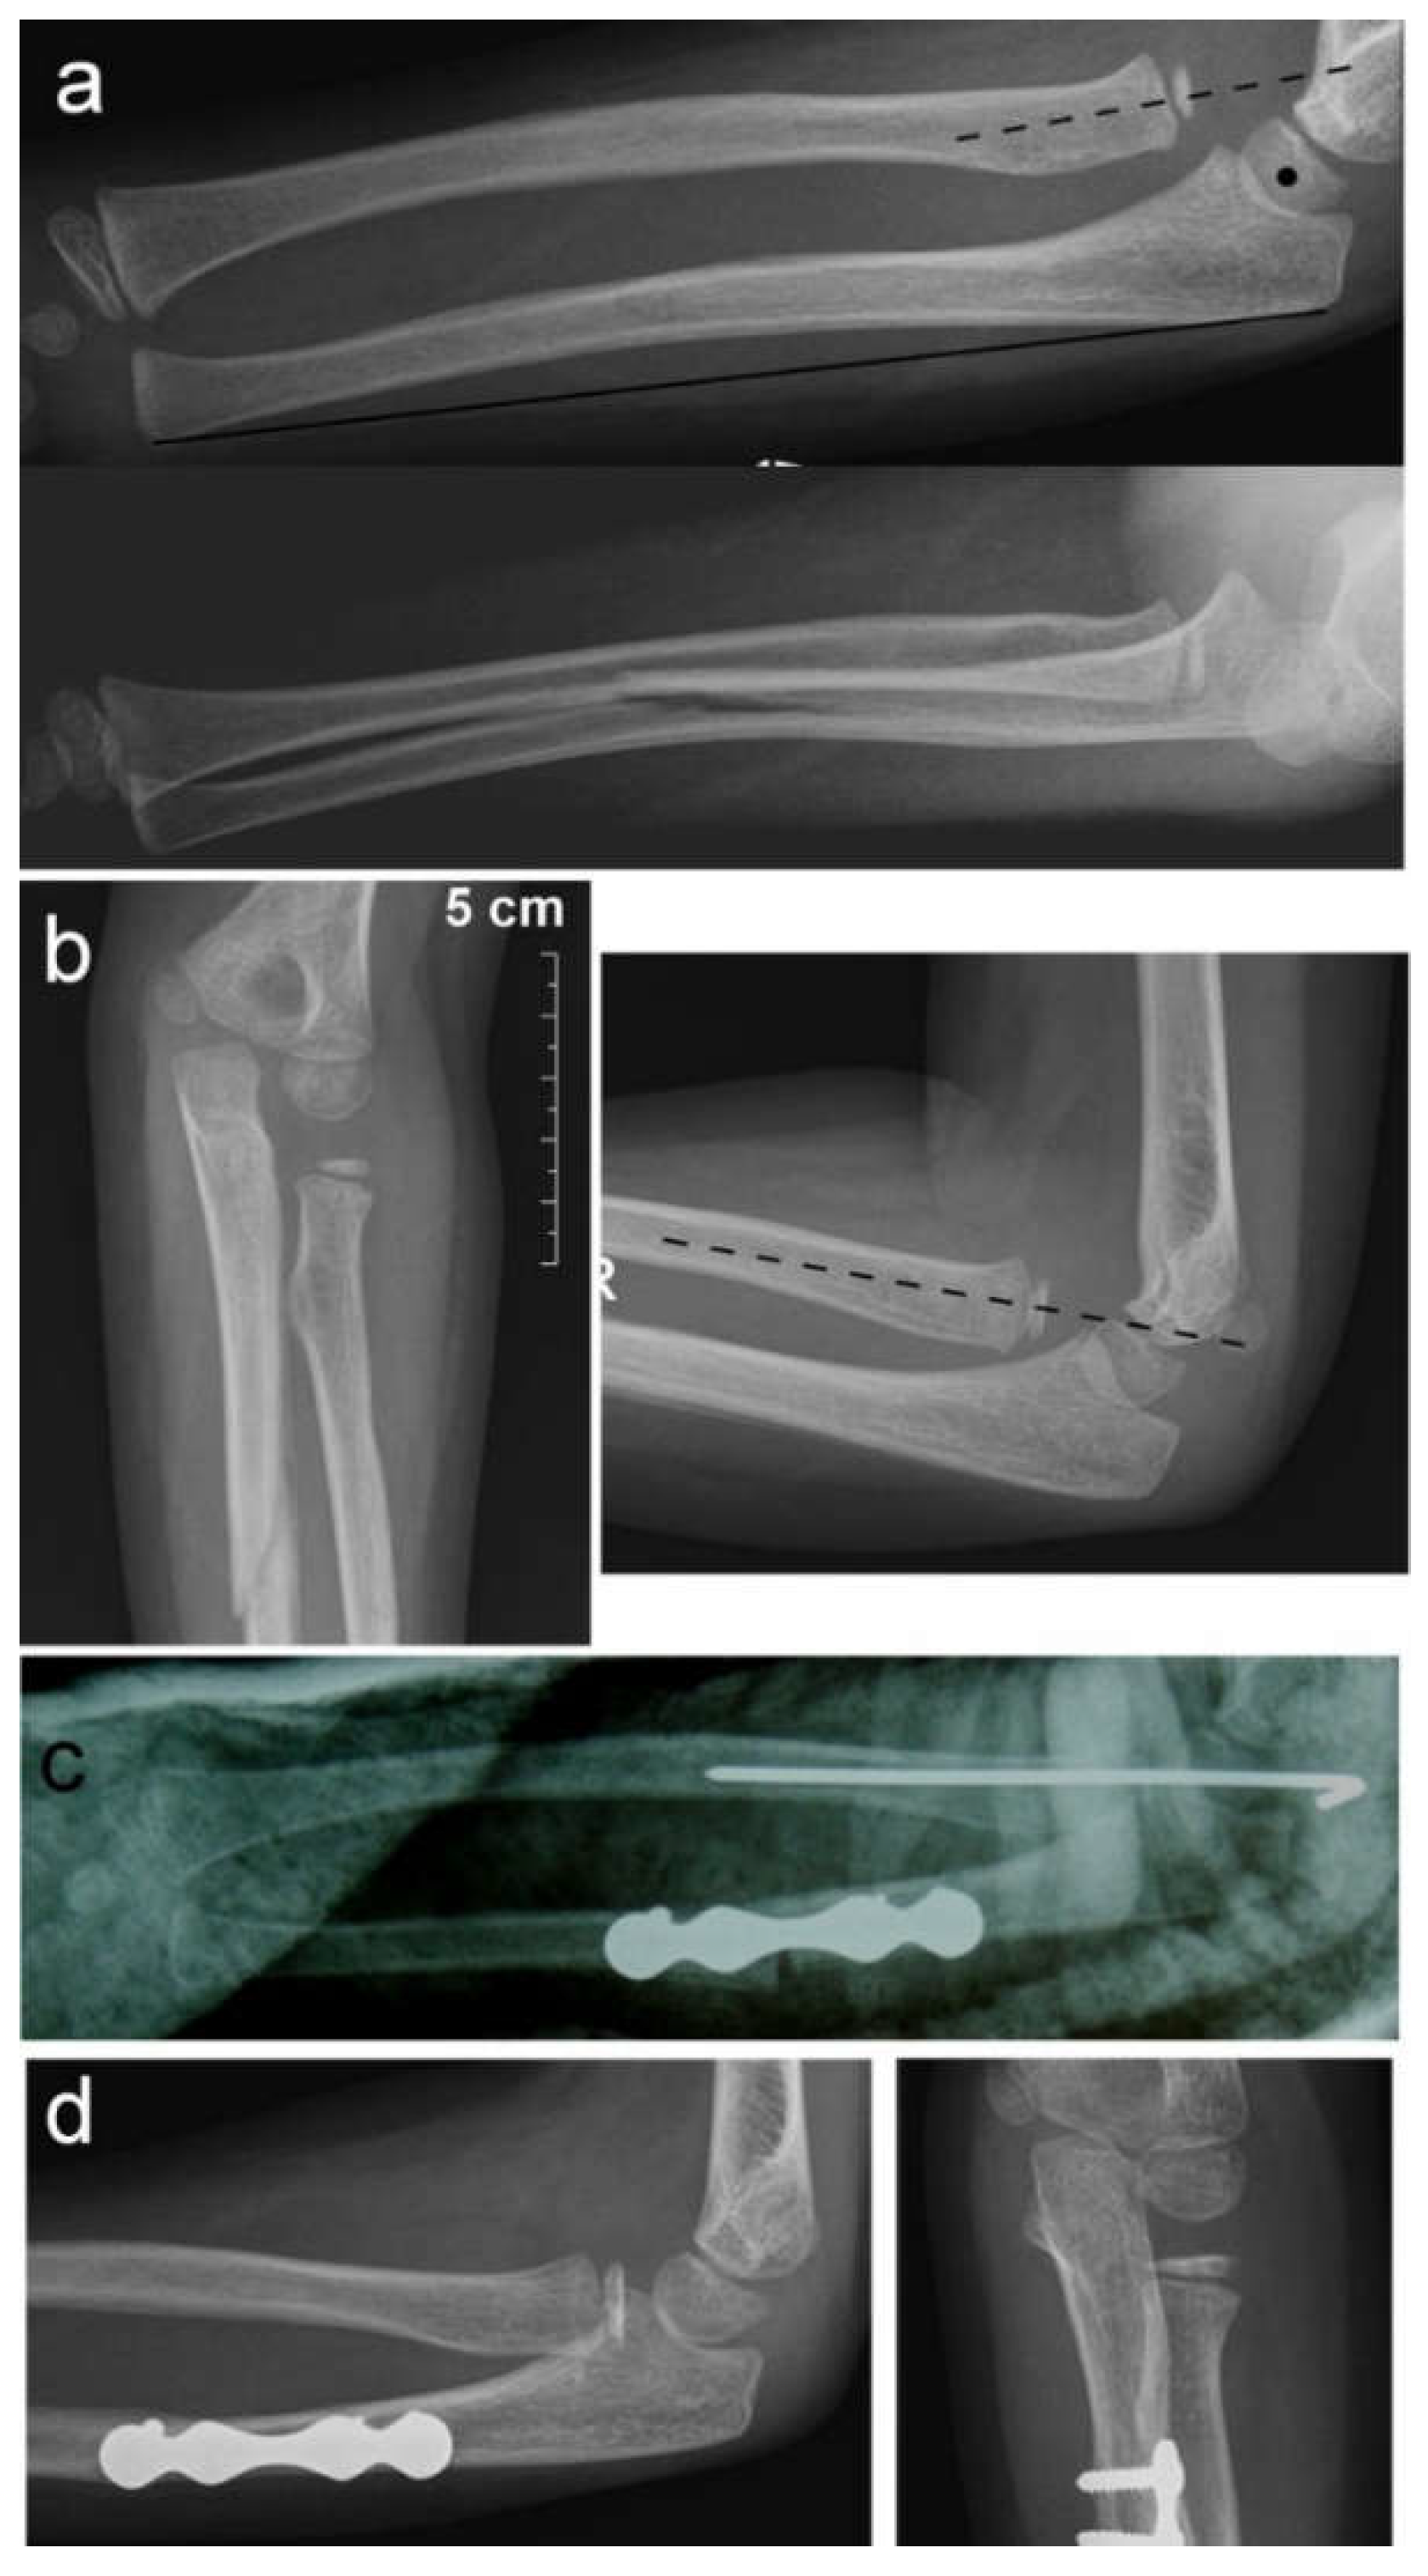

Nine patients had a Bado type I injury, with the radial head displaced anteriorly, and four patients had a Bado type III injury, with lateral and anterior radial head displacement. All patients were treated as soon as possible after a diagnosis of the missed Monteggia fracture was established. The period from diagnosis to surgery varied from 2 days to 2 weeks. An autologous bone graft, harvested from the iliac crest, was used in only one case to fill the gap after osteotomy of the ulna. Another nine osteotomies of the ulna and three osteotomies of the radius healed without bone grafting. All osteotomies of the ulna and two osteotomies of the radius were stabilized with plates and 4–8 screws (Figure 1 and Figure 2).

All the patients in our study were operated on shortly after being diagnosed with a chronic Monteggia lesion. However, there is no need to hurry. Thorough preoperative planning of the reconstructive procedure is very important. A set of correct radiographs in true AP and lateral projection of both injured and uninjured forearms should be obtained [9]. If any discrepancy in the physiological curve of the ulna exists, it should be corrected by ulnar osteotomy. Straightening the natural ulnar curve may result in an incomplete reduction of the radial head, re-dislocation or even late dislocation [24]. We observed re-dislocation of a reduced radial head in one patient as the cause of their chronic Monteggia lesion. His ulna fracture was originally stabilized with a retrograde elastic titanium nail, but progressive loss of reduction with angulation of the ulna occurred. That was left unnoticed until the follow-up for cast removal, which was 4 weeks after the surgery. Revision and fixation with a plate and screws were subsequently performed. We believe that retrograde ESIN may provide insufficient stabilization of the ulnar fracture in a Monteggia injury. Anterograde ESIN through the olecranon entry point may be a better solution. Alternatively, open reduction and plating of the ulna may be performed. If malalignment of the ulna exists, then an osteotomy of the ulna should be the first step in the treatment of chronic Monteggia fractures, especially 3–4 months from the initial injury. A posterior angulation and elongation osteotomy of the ulna, as described by Bouyala [25], is currently the preferred method. Performing an osteotomy high in the metaphyseal region of the proximal third of the ulna may decrease the risk of delayed union or nonunion. Eight of our patients were treated this way (Figure 1). Other authors prefer a more distal osteotomy at the site of maximal angulation of the ulna [26]. Sliding [2] and “Z”-lengthening [27] osteotomies of the ulna have been recently published. In two of our patients, correction of ulnar angulation was performed at the level of a fracture of the ulna. Both patients underwent surgery 5 weeks after their injury, and their fractures, although consolidated, were not completely healed; we decided to correct the deformity at that level (Figure 2). Kim et al. [28] recently performed a 3-dimensional analysis of the deformation of the ulna in patients with chronic radial head dislocation. They found not only angulation but a complex torsional deformity of the ulna. This may explain why a simple angulation-lengthening osteotomy of the ulna may not be completely effective in all cases, especially in Bado type III cases, as reported by Delpont et al. [14] and was observed in one of our cases. Correction of such a complex deformity requires complex correction in two or three planes.

Figure 2. Ulnar osteotomy for chronic Monteggia lesion. (a) Radial head dislocation (dotted line) and ulnar angulation (heavy line) left unnoticed on initial X-rays; (b) chronic radial head dislocation and consolidation of ulnar fracture after cast removal at 4 weeks; (c) angulation osteotomy at the level of the fracture stabilized with a plate and screws and transcapitellar radial head fixation; (d) healed ulnar osteotomy and reduced radial head prior to hardware removal.